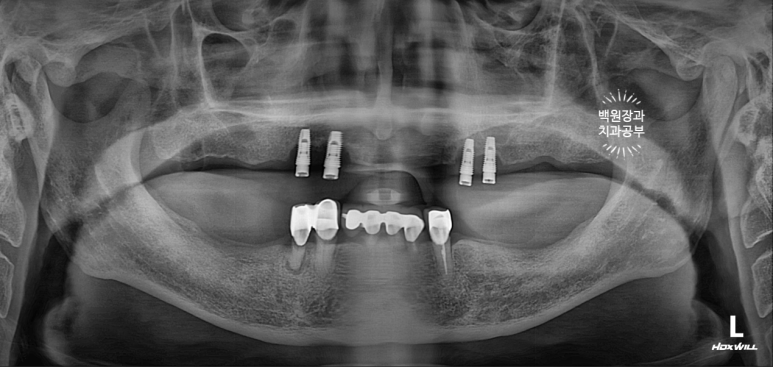

70대 중반 남자 환자분이셨습니다.

위턱에 네개의 임플란트를 이용한 임플란트틀니를 5년 동안 사용하고 계셨는데, 계속 고름이 나오신다는거에요...

노란 점선이 보이시나요? 잇몸뼈의 높이입니다.

상당한 양의 임플란트 주변 뼈가 녹아서 없어져 버린것을 보실 수 있어요.

환자분은 임플란트를 엄청 빼고싶어 하셨습니다.